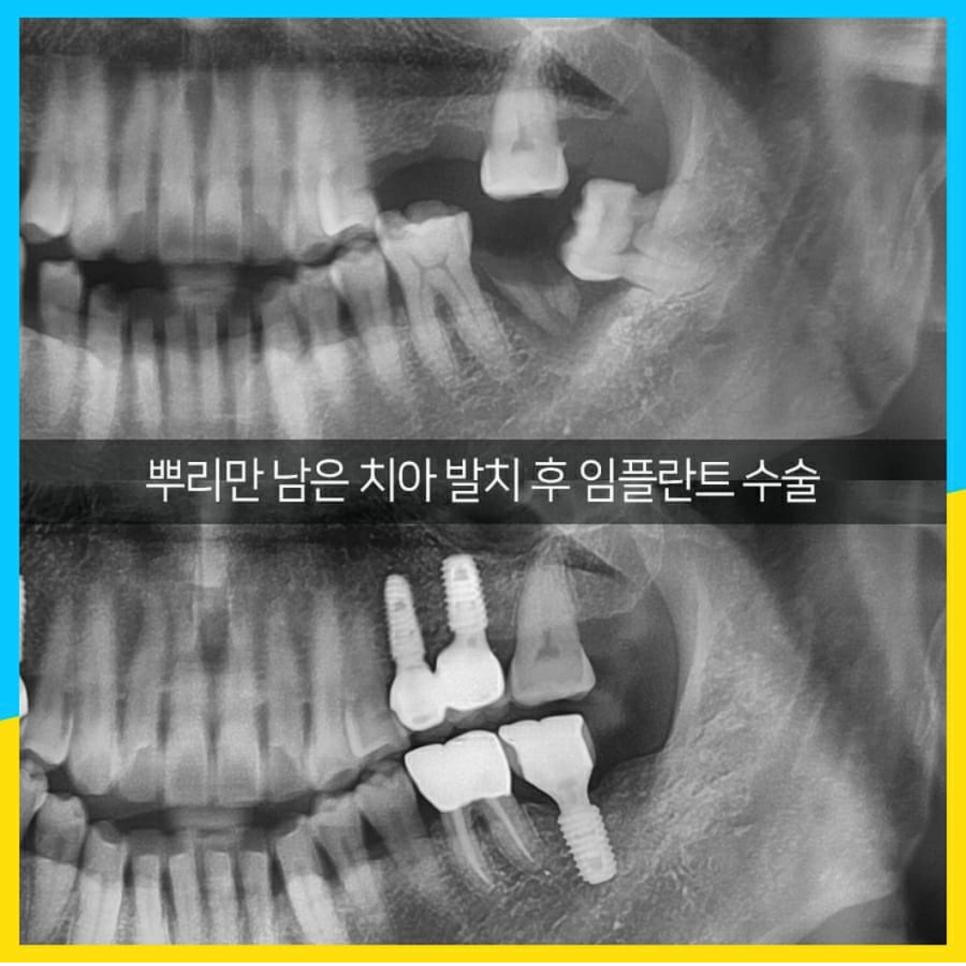

이가 뿌리만 남은 채 오래 방치되었네요.

치아 머리부분이 없기 때문에 이 역시 상실과 같아요.

당연히 옆 치아가 쓰러지는 것은 물론, 이 경우는 아래 이도 위로 솟아 올랐네요.

옆이든 위 혹은 아래든 상실 공간으로

치아가 이동하는 것을 모르셨기 때문이겠죠.

이번엔 이미 진료가 되어 있는 이를 잘 관리하지 않아서 충치가 생겼고,

결국 부러져 어쩔 수 없이 이를 뽑았습니다.

이 케이스는 잇몸뼈의 손실이 없어 발치즉시식립이 가능!

바로 임플란트 수술을 진행하였죠.